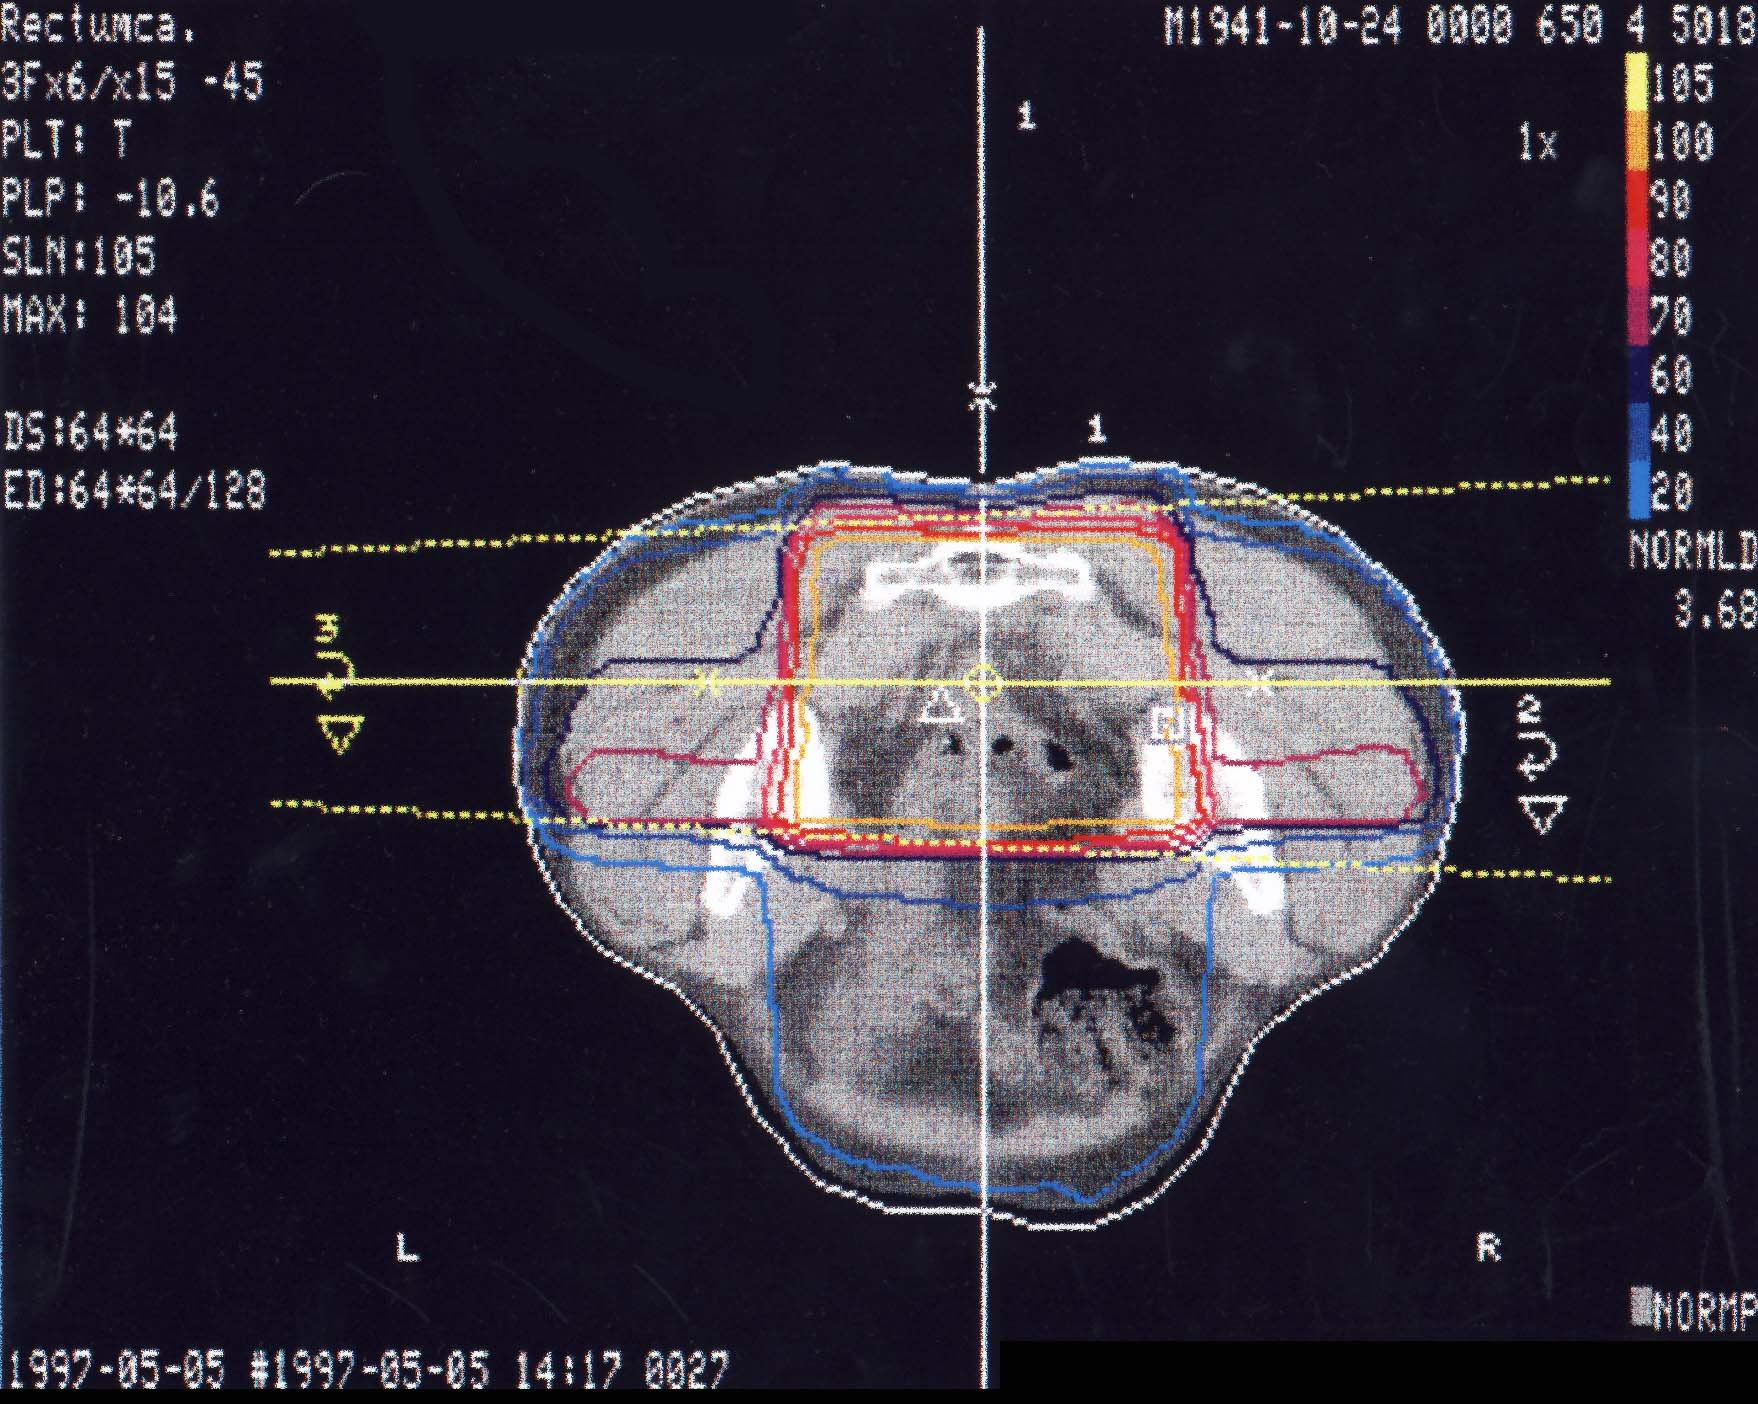

Rektumkarzinom (Enddarm): Bestrahlungsplan